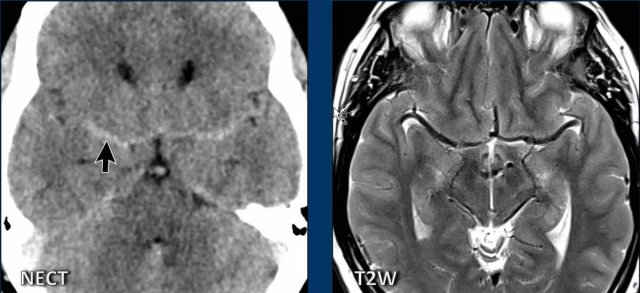

These images are of a 57-year-old male , who presented with headaches and vomiting.

He was alert and there were no abnormalities at neurologic examination.

Images

The symmetrical density in the subarachnoid space was first regarded as sign of a subarachnoid hemorrhage, which seems a reasonable idea.

There is obliteration of the basal cisterns indicative of a descending transtentorial herniation.

CTA was performed, but did not show any aneurysm.

On the MRI it becomes clear, that the bilateral dense structures, that were seen on the CT, are the middle cerebral arteries.

On a CT due to the lack of

surrounding CSF they appear more dense than usual.

The MRI also shows midbrain sagging, seen on the axial image as as an abnormal shape and on the sagittal image as a short distance between the mamillary bodies and the pons.

There is a convex undersurface of the transverse sinus.

We can conclude that this is a case of SIH.